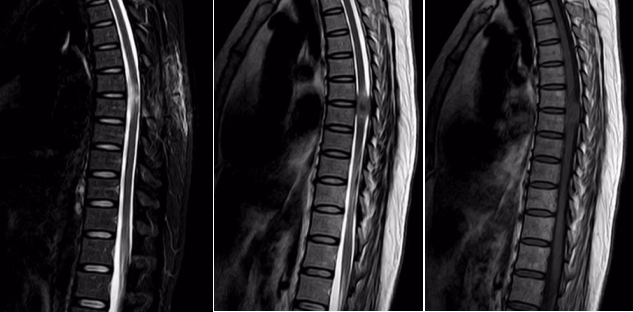

一位女性患者,11个月前没有明显诱因出现双下肢麻木、无力症状,同时伴有排便无力和间歇性跛行的情况,当时并未引起重视。一段时间后,病情逐渐加重,10天前竟严重到无法行走。为寻求治疗,患者来到我院脑外科就诊。门诊通过胸椎 MRI+增强检查发现,胸6-7椎管内左缘髓外硬膜下富血供肿瘤,再结合CT检查后,考虑脊膜瘤,于是以“椎管内占位性病变”将患者收入脑外科住院治疗。

入院后,脑外科团队积极开展术前准备工作。经过详细诊断,基本确定为椎管内肿瘤,脊膜瘤的可能性最大,决定为患者实施肿瘤切除术。术中可见肿瘤呈砂砾状,大小约1.5×2.2cm,颜色呈灰白色,血供丰富且质地坚韧,相应位置的硬脊膜增厚,脊髓受压明显且向右移位,不过幸运的是,肿瘤与脊髓并无明显粘连。在显微镜下,医护人员小心翼翼地将肿瘤分离,严密保护脊髓,最终分块将肿瘤完全切除,病理诊断结果为脊膜瘤。患者恢复良好,现已顺利出院。